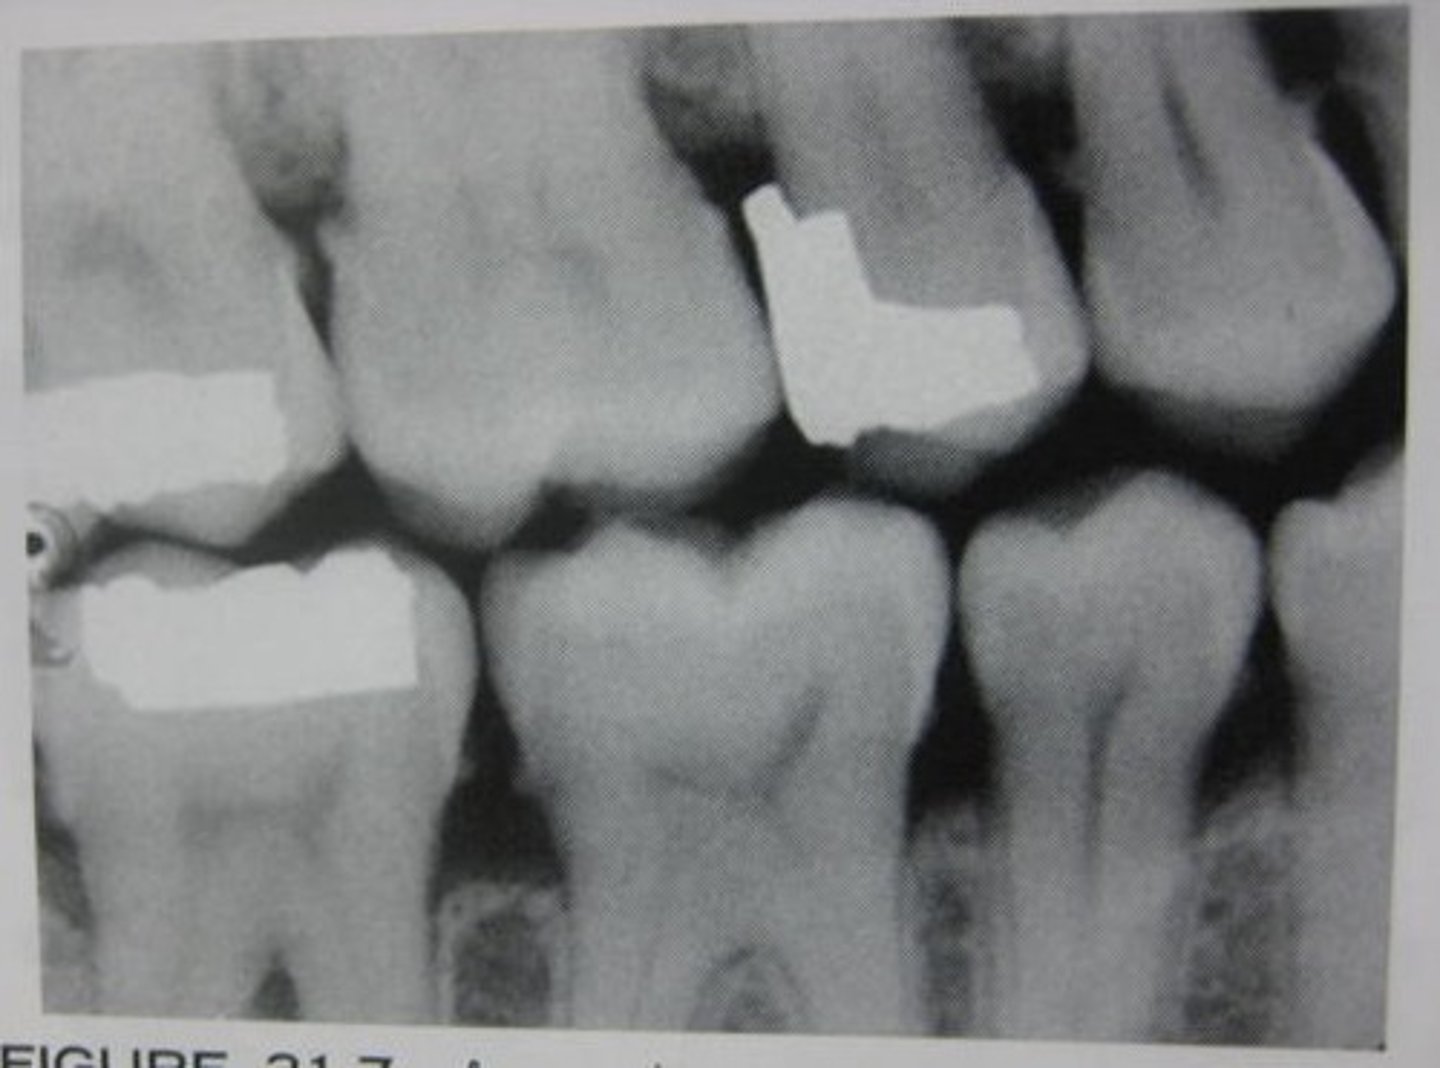

MOD amalgam

overhang

PINS

calculus